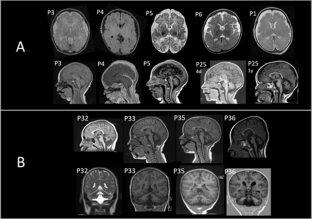

BRAT1 biallelic variants are associated with rigidity and multifocal seizure syndrome, lethal neonatal (RMFSL), and neurodevelopmental disorder associating cerebellar atrophy with or without seizures syndrome (NEDCAS). To date, forty individuals have been reported in the literature. We collected clinical and molecular data from 57 additional cases allowing us to study a large cohort of 97 individuals and draw phenotype-genotype correlations. Fifty-nine individuals presented with BRAT1-related RMFSL phenotype. Most of them had no psychomotor acquisition (100%), epilepsy (100%), microcephaly (91%), limb rigidity (93%), and died prematurely (93%). Thirty-eight individuals presented a non-lethal phenotype of BRAT1-related NEDCAS phenotype. Seventy-six percent of the patients in this group were able to walk and 68% were able to say at least a few words. Most of them had cerebellar ataxia (82%), axial hypotonia (79%) and cerebellar atrophy (100%). Genotype-phenotype correlations in our cohort revealed that biallelic nonsense, frameshift or inframe deletion/insertion variants result in the severe BRAT1-related RMFSL phenotype (46/46; 100%). In contrast, genotypes with at least one missense were more likely associated with NEDCAS (28/34; 82%). The phenotype of patients carrying splice variants was variable: 41% presented with RMFSL (7/17) and 59% with NEDCAS (10/17).